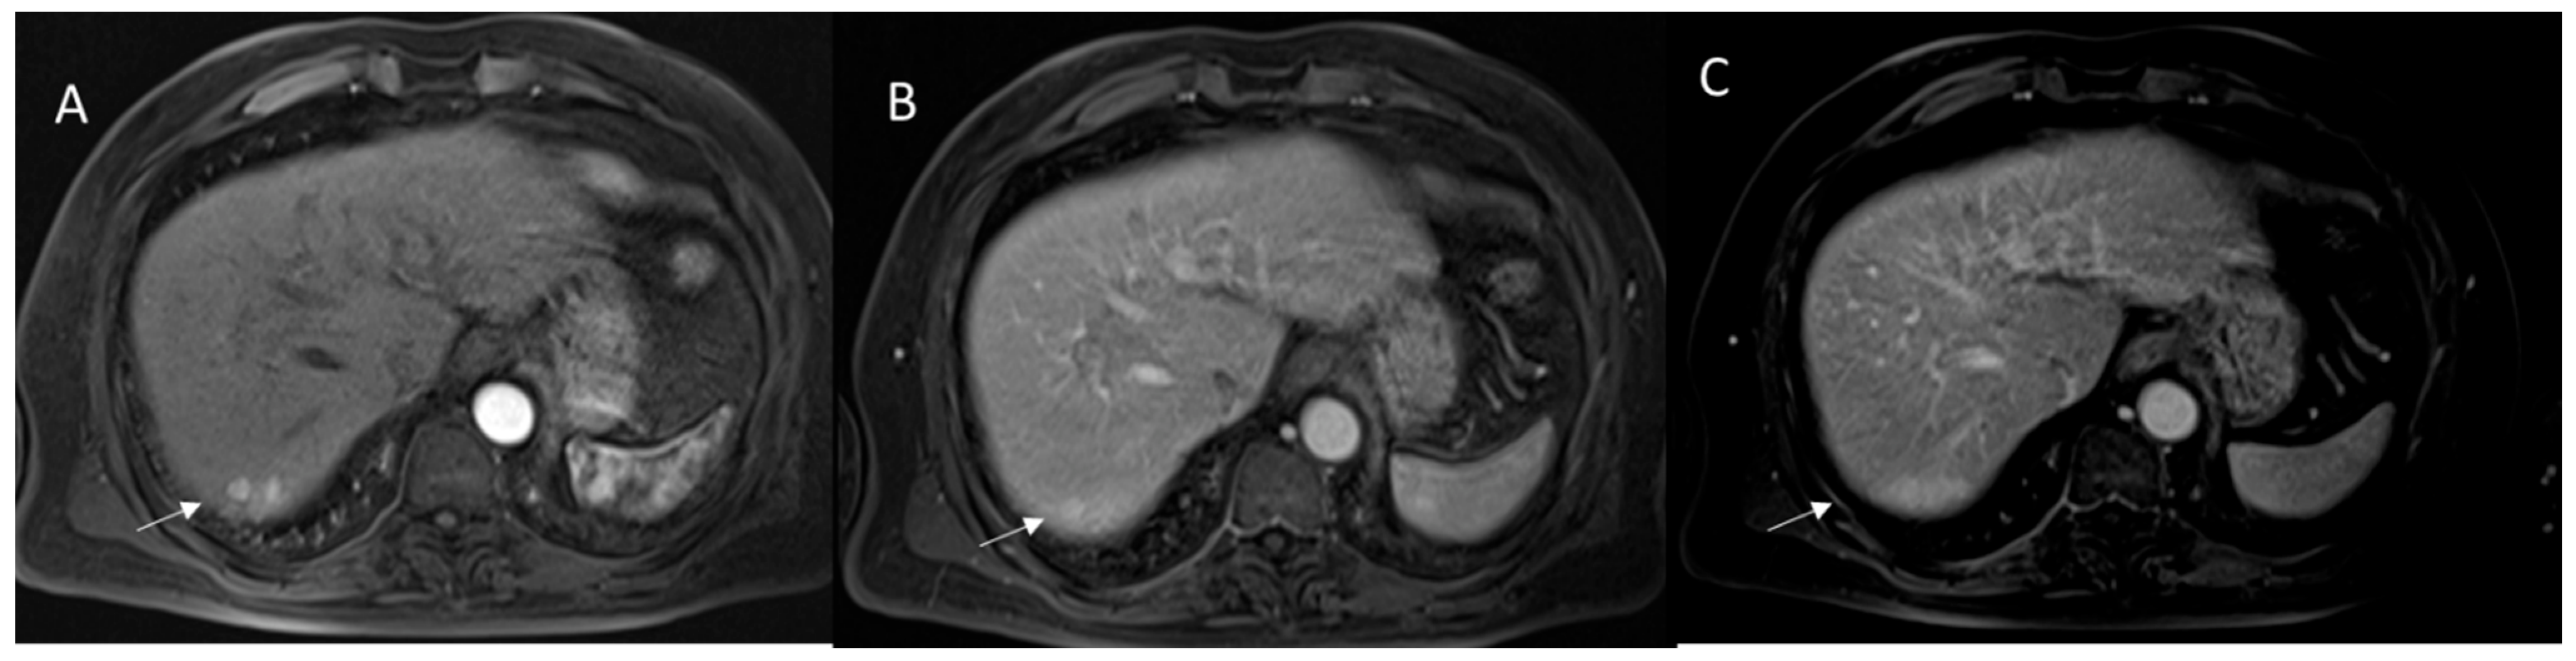

2.4. LI-RADS Treatment Response Algorithm

2.2. CT/MRI LI-RADS

2.2.3. HCC Diagnosis